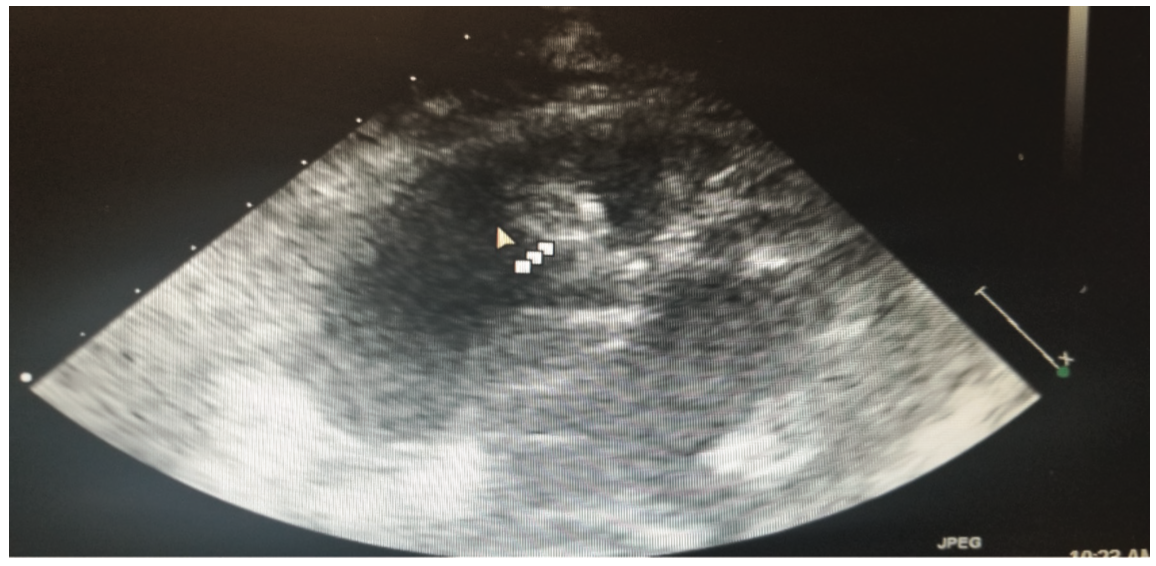

This is a 58-year-old female with a history of tuberous sclerosis. Transthoracic echocardiogram images demonstrated a heterogeneous mass in the mid right ventricle attached to the septum and the moderator band (Figures 1-6). The mass looked similar to what was seen on a transthoracic echocardiogram from a year prior.

One of the major differentials for this mass was thought to be cardiac rhabdomyoma, given the patient’s history of tuberous sclerosis with known renal angiomyolipomas. Cardiac rhabdomyomas are usually associated with tuberous sclerosis complex, which is a genetic disorder characterized by hamartomas in multiple organs. Rhabdomyomas may develop at any location in the heart, but the most common locations are ventricular and septal walls.